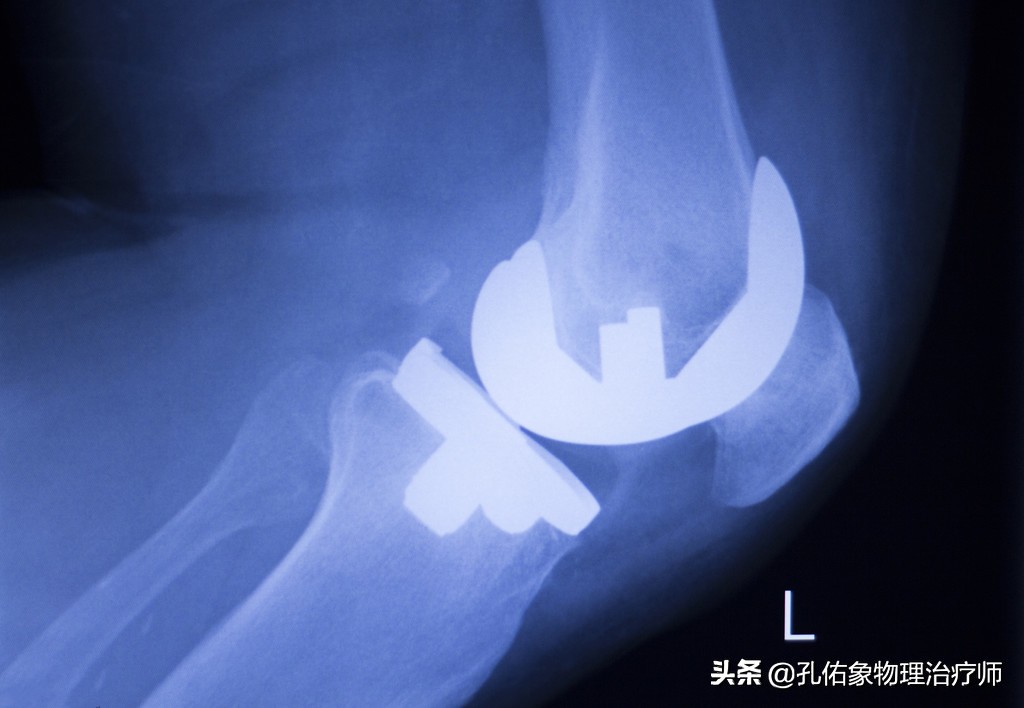

1.避免手术

膝痛在早期时,往往只体现出局部的疼痛,局部的炎症肿胀;但是随着自身的不注意,慢慢的力学改变,膝盖骨与大腿骨撞击就会引起膝盖骨下面的软骨损伤,逐年累月的血液循环障碍、骨质增生、骨赘形成;到这个时候要解决问题,只有通过手术,关节镜下处理或是直接用一个假的膝关节换进去。

我目前接诊着一个病人,还是医务工作者,才年仅42岁呀,就把膝关节给换了;因为我上面所写的的,在她身上都可以淋淋尽致的体现出来。

要是你在刚发现膝痛时,就早早选择正确恰当的方法治疗,绝对可以避免将来的手术。